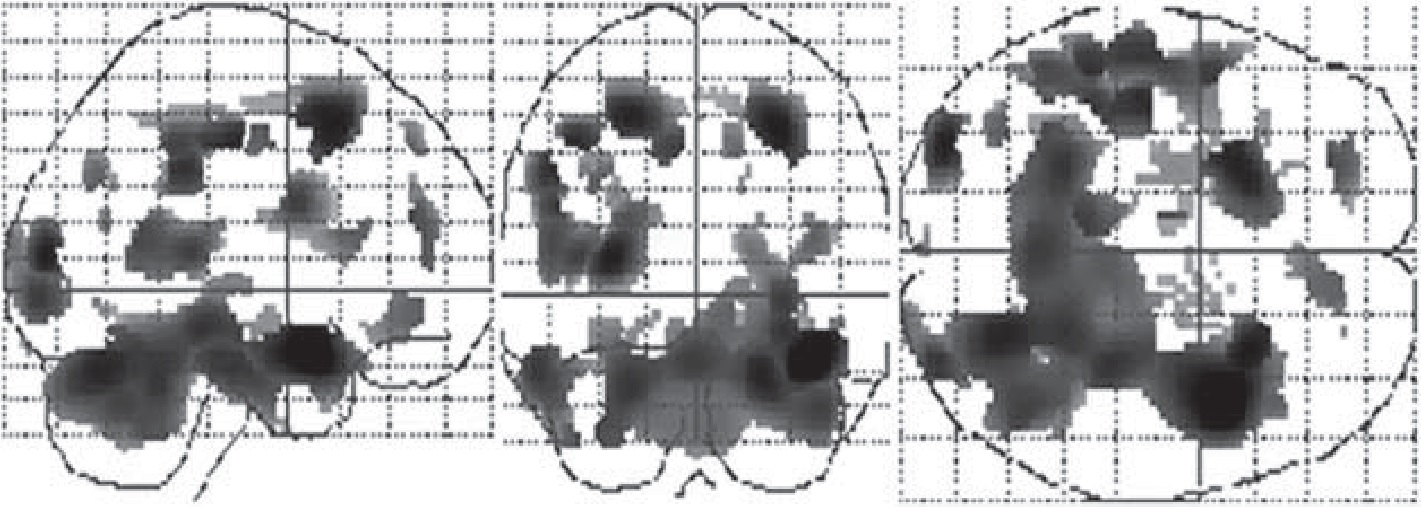

После двух курсов МПБТ постепенная положительная динамика энергетического метаболизма (по данным позитронно-эмиссионной томографии) у пациентки К. была выявлена в лобной, височной, затылочной долях, передних подкорковых ядрах обоих полушарий, таламусе, стволе мозга, мозжечке (рис. 3). Это соответствует представленным выше «общим» данным.

Рис. 3. Статистическая непараметрическая схема областей мозга с увеличением скорости метаболизма глюкозы в динамике после двух курсов МПБТ по данным позитронно-эмиссионной томографии